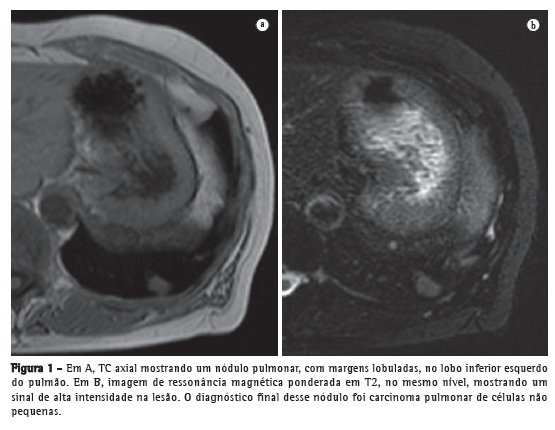

Indicações clínicas da RM de pulmãoEstadiamento de tumores pulmonaresDetecção e caracterização de nódulos pulmonaresEstima-se que todo ano nos Estados Unidos haja aproximadamente 150.000 novos casos de nódulos pulmonares observados em radiografia simples de tórax.(9) Uma meta-análise recente relatou que a TC dinâmica e a RM, ambas as quais são métodos não invasivos, são igualmente acuradas para fazer a distinção entre nódulos pulmonares solitários benignos e malignos e que as diferenças entre os dois exames são insignificantes.(10) Os autores da meta-análise constataram que, para os 10 exames com TC dinâmica, a RM apresentou sensibilidade combinada de 93% (IC95%: 0,88-0,97) e especificidade combinada de 76% (IC95%: 0,68-0,97).(10) Koyama et al.(11) relataram que a RM de pulmão sem contraste é tão eficiente quanto a TC com multidetectores e cortes finos para detectar nódulos malignos. Os autores também constataram que a taxa global de detecção de nódulos em cada sequência de RM (82,5%) foi significativamente menor que a da TC com multidetectores (97,0%), embora não tenha havido diferença significativa entre as duas técnicas no que tange à taxa de detecção de nódulos malignos.(11) A Figura 1 mostra uma comparação de imagens obtidas com as duas modalidades.